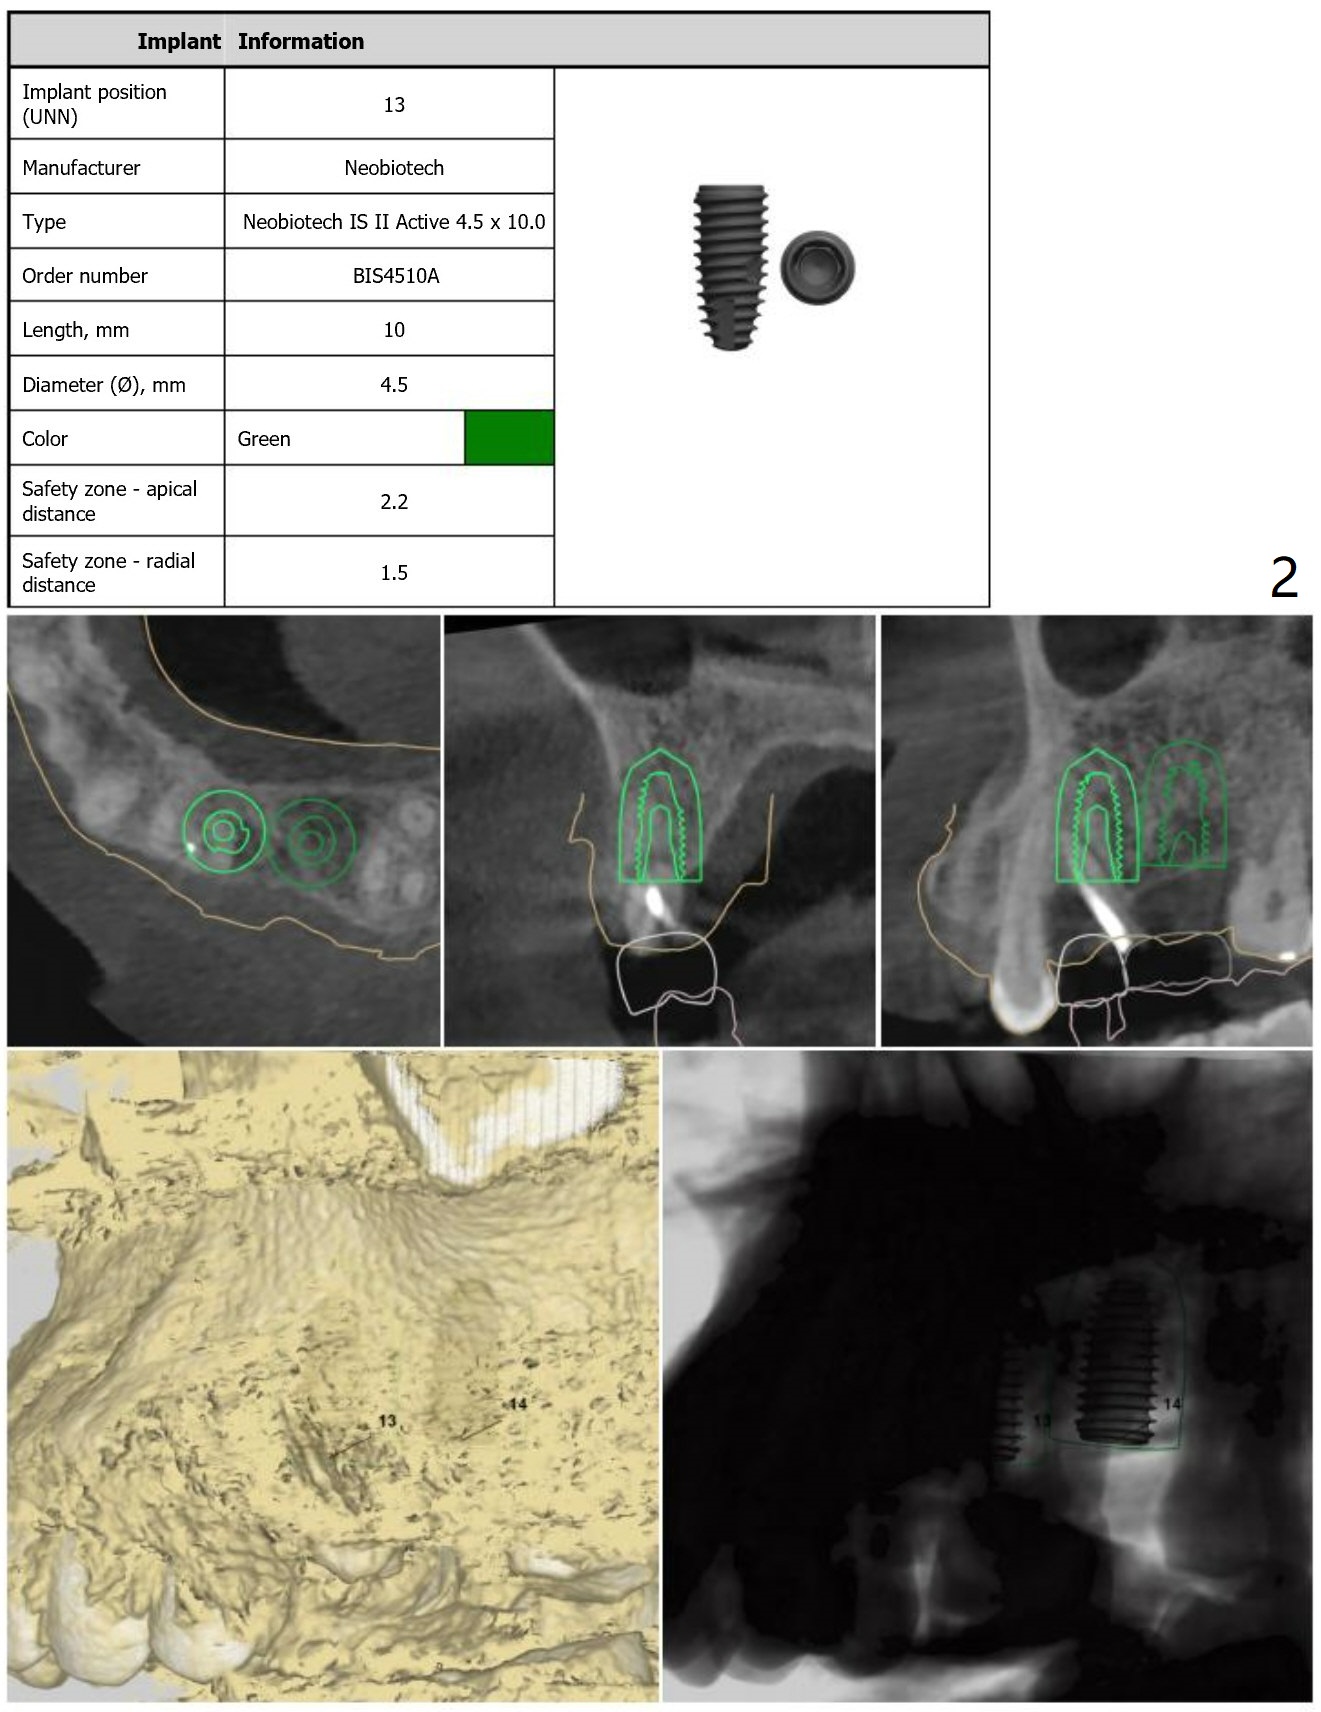

Return to Upper Molar Premolar Immediate Implant, Trajectory, Metronidazole